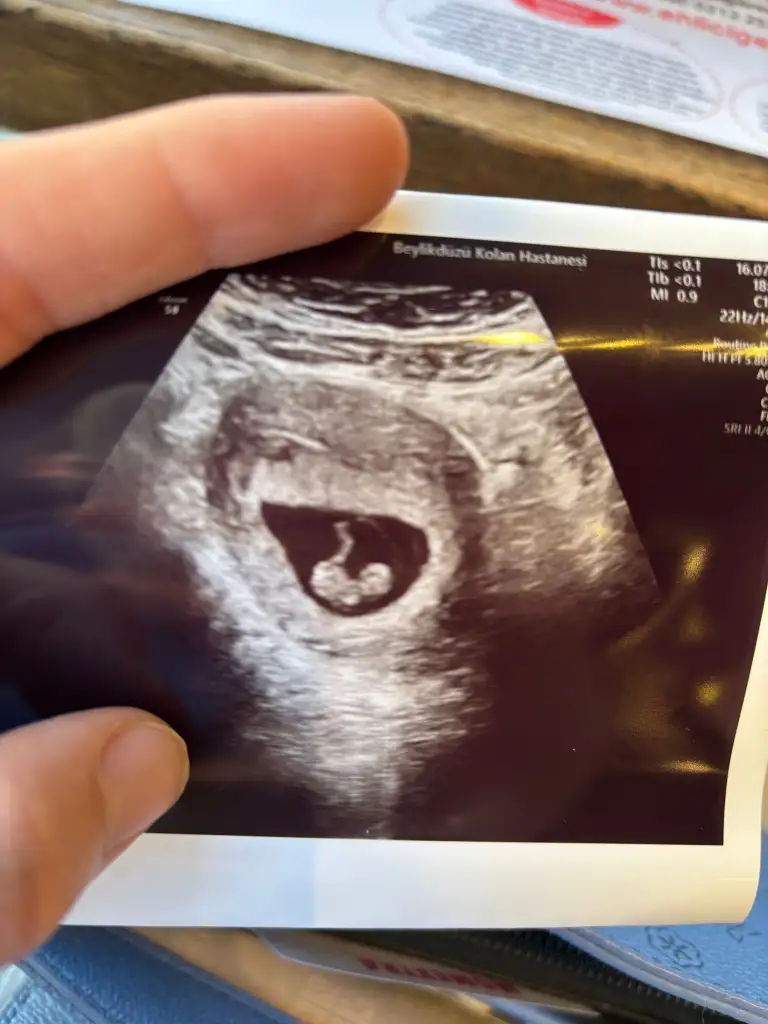

Sizce benim nedir 11+1rica ederim kesenin şeklinden

Erkeğe benziyor amaSizce benim nedir 11+1

hahaha Instagram da 3 kişiye baktırdım 2 si kız 1 erkek diyor ve . Yapay zekaya . Sordum Yeni MHP teorisine göre kız ramzi göre erkek keseye göre kızErkeğe benziyor ama

Canım seninkisinin fetus çok küçük belli olmuyor